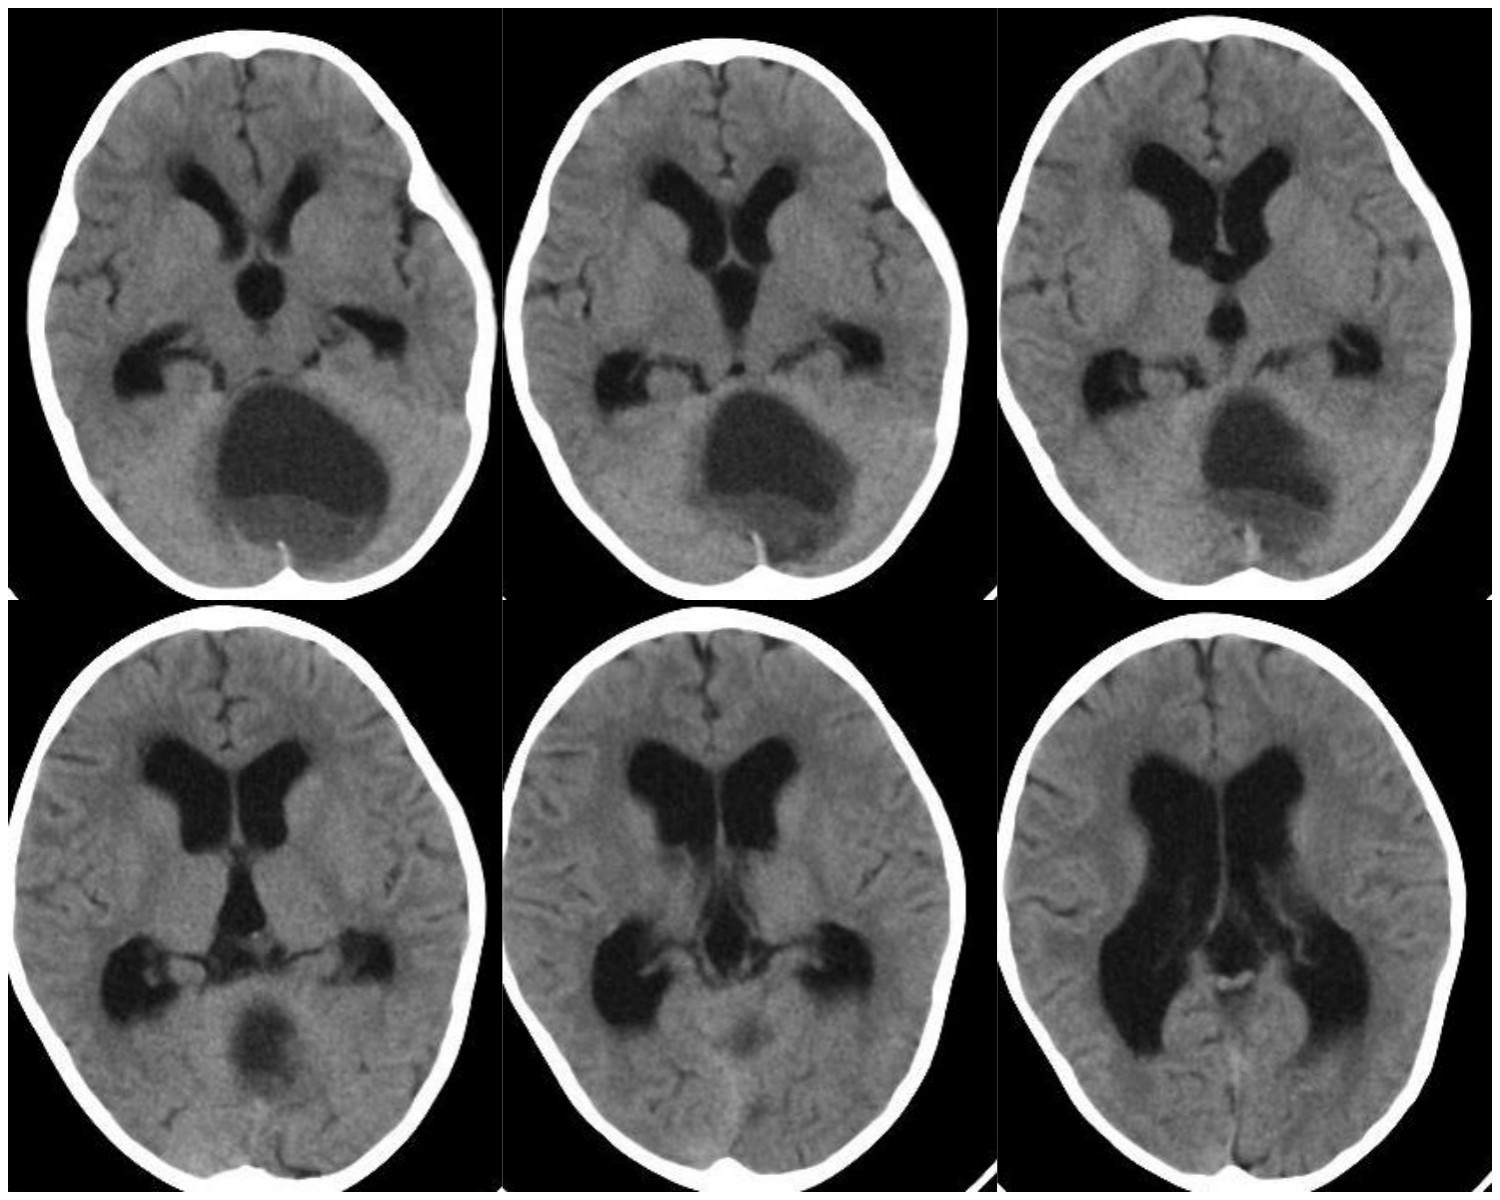

患儿高**,女,3岁,因“走路不稳4月、加重伴头晕1周”入院,就诊当地医院,CT检查发现第四脑室可疑占位伴脑积水。就诊我院,头颅磁共振提示后颅凹巨大囊实性占位伴幕上脑积水。

图2 术前增强头颅磁共振